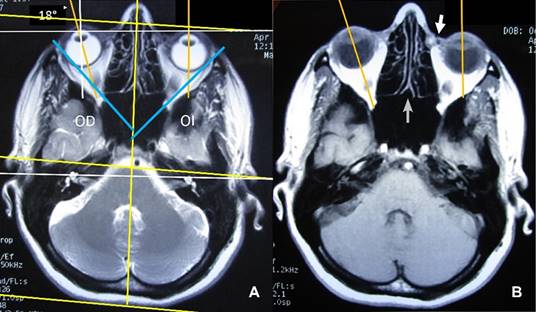

Mujer de 38 años que acude a rehabilitación con diagnóstico de síndrome miofascial de cabeza y cuello de origen en articulación temporomandibular. A la exploración, llamó la atención discreta asimetría facial, y exotropía de ojo derecho. Se le había efectuado resonancia magnética para el estudio de cefalea, en donde se detecta la presencia de plagiocefalia (Figura 1).

Figura 1: Imágenes de resonancia magnética de cráneo, ponderadas en T2. (A) Se muestra plagiocefalia por asimetría de hemicráneo derecho de 18o en relación al eje coronal, además de nacimiento, más anterior de pabellón auricular derecho; se observa asimetría de ejes de las órbitas, con exotropía de ojo derecho por acción del músculo oblicuo mayor derecho. (B) Se aprecia desviación de la línea media hacia la izquierda en relación al eje sagital (flecha gris); presencia del conducto lacrimal óseo izquierdo (flecha blanca) y desviación hacia afuera del eje de ojo derecho (exotropía).

El término “plagiocefalia” fue introducido por Virchow en 1851, sus raíces son πλαγιο (oblicuo, inclinado) y κεφαλή’ (cabeza). Los términos “P anterior” y “P posterior” se usan casi siempre como sinónimo de craneosinostosis unicoronal y lambdoidea respectivamente (malformación del cráneo causada por el cierre prematuro de una sola sutura craneal); las asimetrías craneales que no se deben a la fusión temprana de una sutura craneal, se definen en relación con sus factores causales como plagiocefalia posicional o plagiocefalia ocular. La plagiocefalia constituye 85% de los casos de deformidades craneales plásticas y aparece más en el género masculino con relación 2:1 y afecta con más frecuencia el lado derecho (2,7:1 niños; 1:1 en niñas); por lo regular aparece en el plano axial, aunque no son raras las formas mixtas axiales, sagitales y coronales.1 En la plagiocefalia craneosinostótica no sindromática existe incremento de estrabismo y astigmatismo, observándose exotropía con mayor frecuencia que en la población general.

Las manifestaciones craneales incluyen: aplanamiento de la frente y acortamiento del techo orbital en el lado afectado, existe crecimiento compensatorio del cráneo en el lado contralateral, lo que resulta en asimetría facial, el lado afectado parece más grande y cóncavo, mientras que el lado compensatorio es más pequeño y convexo cuando se hace referencia a la línea media. La función del músculo oblicuo superior2 del lado afectado se reduce por acortamiento del techo orbitario, lo que ocasiona, como en el caso presentado, exotropía derecha constante e hipotropía, astigmatismo hipermetrópico ambliopía con fijación excéntrica.3 De manera específica en adultos la plagiocefalia es a menudo desapercibida.4